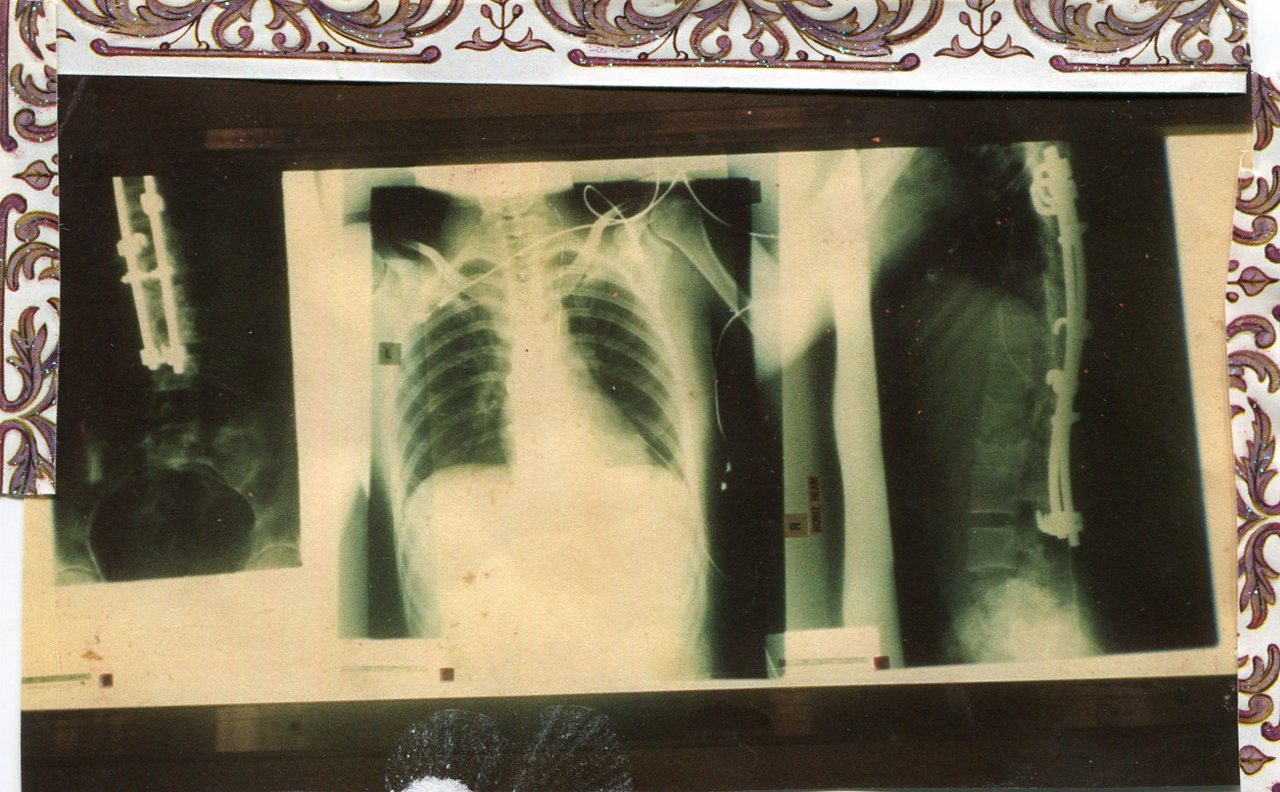

All the dreadful diagnosis and radiology reports are stored somewhere deep in the recesses of my office. The scripts are filled and the date when new ones will be required have been diarised. Some days, the pain can be a reasonable 6/10. You need to work; you want to work. You feel okay, until you’re not. Trying to engage with people whilst sharp pieces of bone are lodged in your spinal canal for all eternity is tiresome. You have to rise above; transcend it. You need to focus more; work harder than others might.